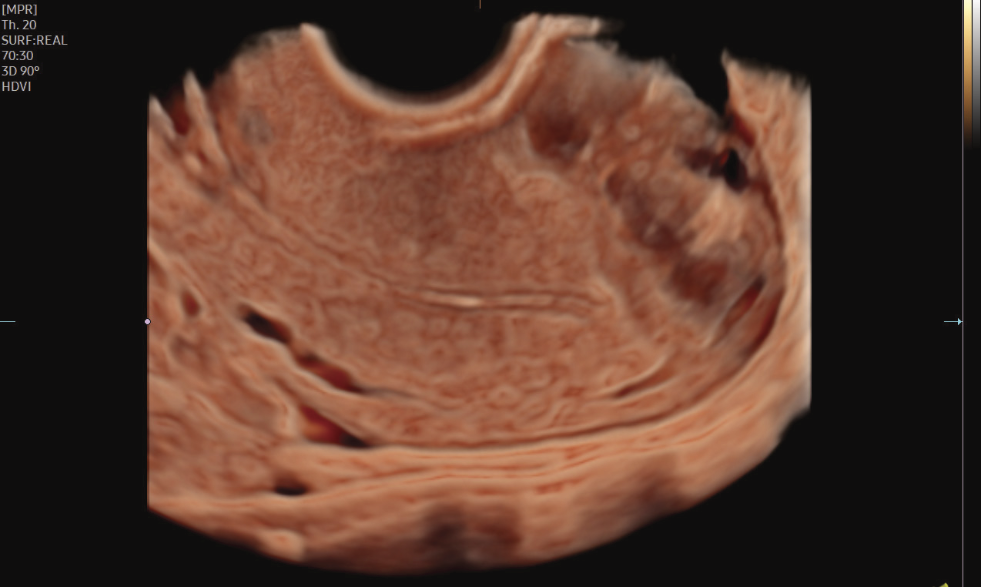

• Recursos exclusivos em 3D: RealisticVue™, CrystalVue™, PortraitVue™, Luminant™.

Imagens Clínicas

Ferramentas com IA para exames gineco-obstétricos